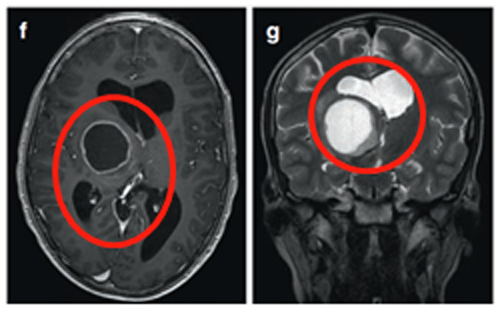

9岁男孩-丘脑结节肿瘤

患者为一名9岁男童,左面部、上肢和下肢有3周的急性病史,持续轻微口齿不清三个月以上。他还有多处咖啡色的斑点和腋窝雀斑。被诊断患有注意缺陷多动障碍,这些症状可以归因于器质性病因。

(图6a、b)轴位MRI造影剂及冠状面T2-WI显示一个环形增强的右侧丘脑结节肿瘤。

(图6)

肿瘤累及内侧颞结构(图6c),Rutka教授考虑根据其病情进展制定综合治疗方案,先行经颞中回经脑室入路次全切除肿瘤,组织学为WHO I级毛细胞星形细胞瘤,BRAF重复融合状态为阴性。免疫组化检测BRAF V600E、H3K27M阴性。基因测试证实了NF1基因的变异。术后严密随访患儿术后情况。

(图7)六个月后的影像显示丘脑部分切除和中脑的小肿瘤残留,因此,Rutka教授根据其病情发展量身定制辅助治疗计划,患儿对放疗反应良好。

(图7)